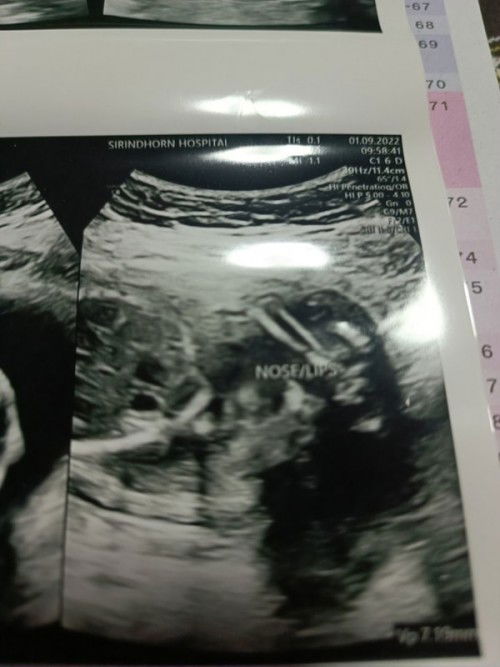

ก่อนหน้านี้น้องดิ้นแรงมากเรารู้สึกตลอดยิ่งเวลานอนพักหรือฟังเพลงเค้าจะดิ้นแรงมาก แต่พอฉีดวัคซีนเข็ม2 ทำไมเรารู้สึกลูกไม่ค่อยดิ้น ดิ้นน้อยลงดิ้นทีก็แทบจะไม่รู้สึกเลยนอนพักก็ไม่รู้สึกฟังเพลงมีรู้สึกบ้างแต่ไม่เท่าก่อนไปฉีด เราฉีดมา5วันแล้วเราไม่ค่อยรู้สึกมา2-3วันแล้วคะ หรือว่าคิดมากไปคะ ท้องแรกคะเลยกังวลมากๆเลยอยากถามแม่ๆคะว่าเคยเป็นกันไหมคะ #ขอบคุณล่วงหน้านะคะ 🙏🏻💞